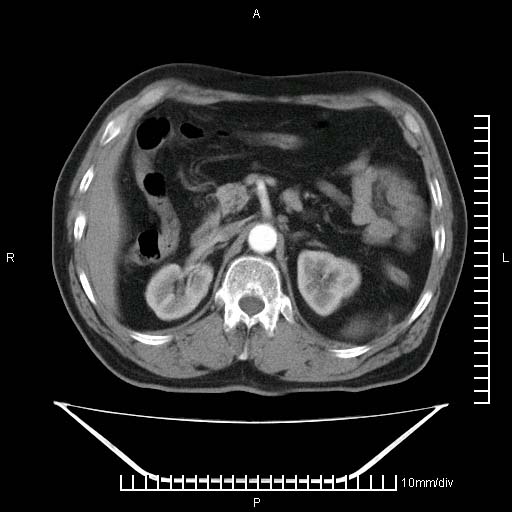

标题: CT25082:肝脏增强:男性,70岁 [打印本页]

标题: CT25082:肝脏增强:男性,70岁

患者以心脏疾病收住院,腹部无明显症状,b超查肝脏有占位。

增强效果不理想。考虑转移,胆囊壁明显增厚,不排除胆囊癌肝转移。

牛眼征,中心坏死无强化,外缘强化,最外缘又见低密度,考虑转移,与脓肿鉴别

肝内多发转移瘤,右下肺炎症并少量胸水。胃壁增厚建议胃镜,胰尾部“病变”为肠管。

1)肝脏多发性转移瘤(不排除胰尾癌转移所致可能)。2)腹水。3)右侧少量胸腔积液。

ct25082 结果:转移瘤

外院mr结果:胰尾恶性占位。